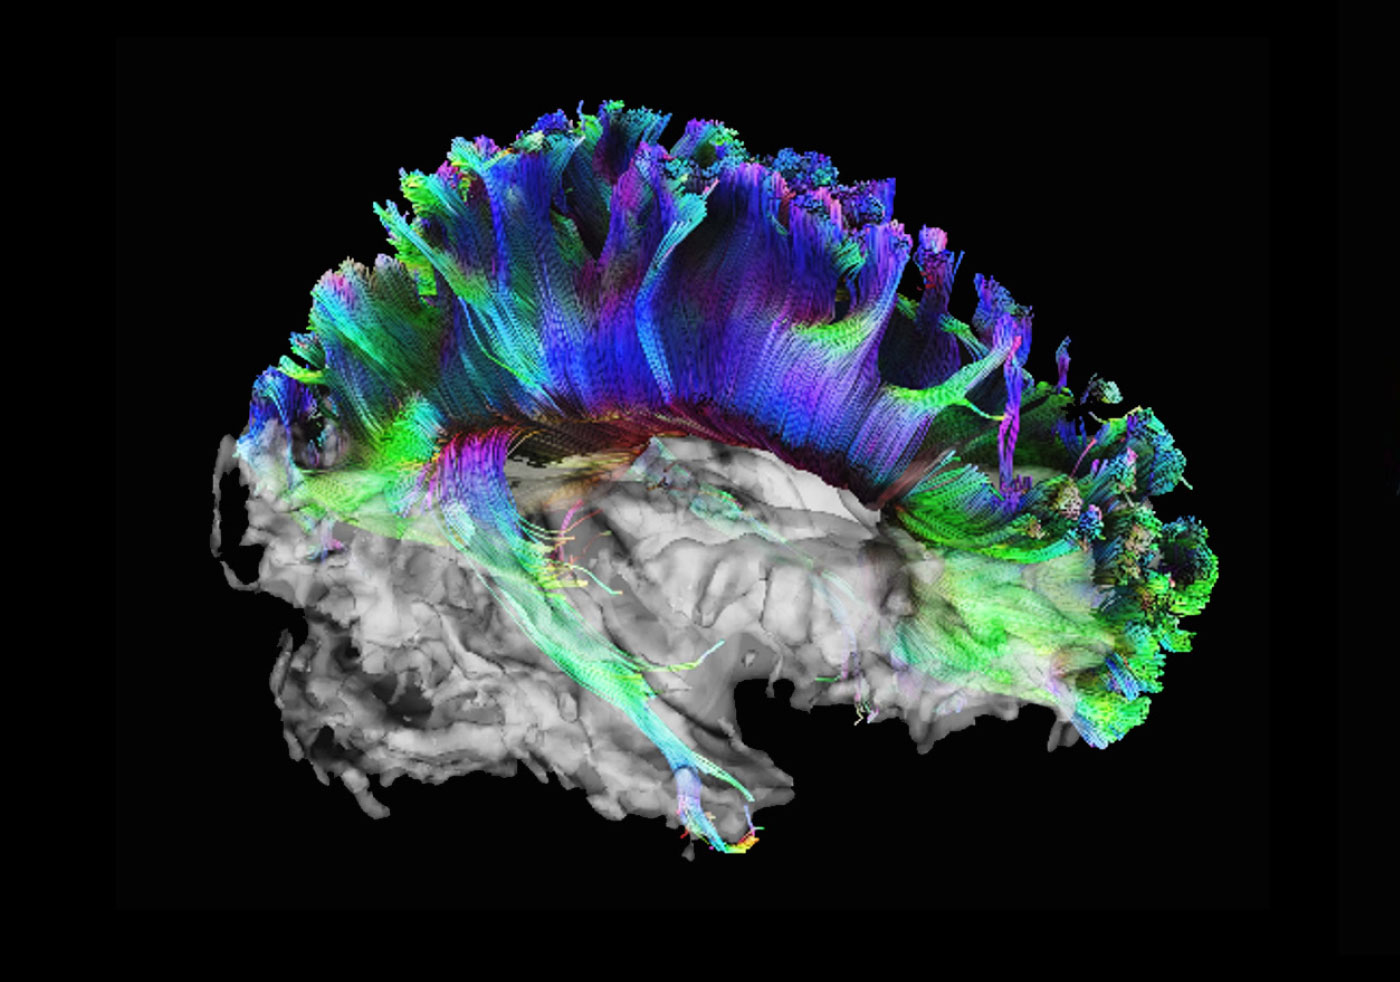

High angular diffusion imaging

The neuroscience team used 257 different directions, 23 b-values and a maximum b-value of 4000 s/mm² to collect the data below in a total scan time of 11 minutes. The higher number of gradient directions combined with multiple b-values not only allows for improved fiber tracking in these examples, but also enhances the analysis of intra-voxel incoherent motion (IVIM) and diffusion kurtosis (DK) effects in one single measurement.

High angular diffusion imaging

The neuroscience team used 257 different directions, 23 b-values and a maximum b-value of 4000 s/mm² to collect the data below in a total scan time of 11 minutes. The higher number of gradient directions combined with multiple b-values not only allows for improved fiber tracking in these examples, but also enhances the analysis of intra-voxel incoherent motion (IVIM) and diffusion kurtosis (DK) effects in one single measurement.